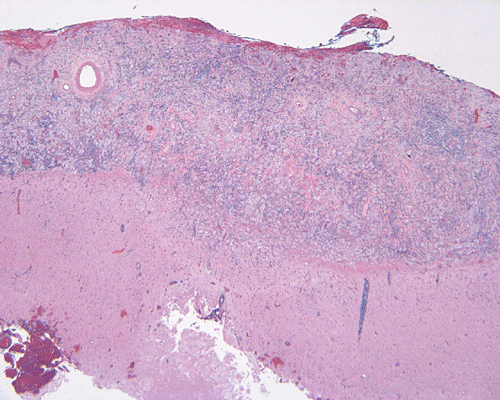

The specimen is in the form of a plaque-like, firm lesion adhered to a layer of brain parenchyma on one side (Panel A) The lesion infiltrate into the underlying brain parenchyma which leads to the formation of an irregular interphase. There is also perivascular accumulation of lymphocytes around blood vessels (Panel B  and C). On low-mangification, the lesion appears to be a mixture of lymphocytes and large cells with foamy histiocytes. The salient feature of the lesion is that of a mixture of mature lymphocytes with large to giant histiocytes (Panel D). The histopathologic picture is rather homogeneous in different parts of the lesion. On high-magnification, the large to giant histiocytes has enlarged nuclei and many of them contain engulfed lymphocytes or polymorphonuclear leukocytes (emperipolesis ) (arrows in Panel E an F).

Grossly, dural based RDD are firm, often plaque like lesions that resemble meningioma but they are firmly adhered to the brain.

Histiologically, the features of cranial RDD are similar to those occurring in the lymphnodes.  Lesions are composed of sheets or syncytia of large, pale histiocytic cells with abundant granular eosinophilic cytoplasm and ill-defined or feathery cytoplasmic borders in a lymphocytic, chronic inflammatory cell background. Extranodal sites commonly exhibit a degree fibrosis and this can obscure the visibility of the histiocytic proliferation. Nuclei of the large histiocytes vary in size and may be large, round and vesicular with smooth nuclear contours 2. A mild degree of cytological atypia is commonly seen.  Most nuclei contain a single small nucleolus, but others possess multiple nucleoli or a single prominent nucleolus. Mitotic figures are usually difficult to detect or are absent altogether. The prominent background of chronic inflammation is largely comprised of a mature plasmacytic infiltrate with interspersed lymphoid follicles 2.  Emperipolesis is consistently found in nodal disease and often is less evident at extranodal sites.  Its recognition is key to correct diagnosis.